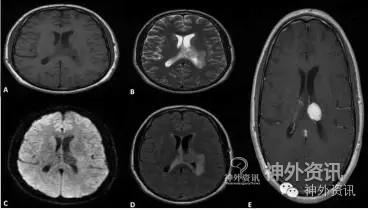

30岁男性患者,主诉进展性复视伴枕部头痛和双侧眼球后疼痛,晨起和夜间头疼加重。体格检查无阳性体征,眼底镜显示视神经乳头水肿。头颅MRI示,左侧脑室内占位性病灶,T1加权略低信号、T2加权低信号;增强扫描病灶呈明显均一强化,无钙化,约2.15×2.11×2.32cm大小;MRI弥散像呈阴性;T2加权FLAIR像显示左侧脑室内略高信号病灶,周围脑水肿(图1)。胸腹部CT检查未见病灶,证明颅内为原发性肿瘤。

图1. 术前颅脑MRI轴位像显示脑室内占位性病灶。A.术前头颅MRI-T1加权像显示,左侧脑室内低信号病灶;B.T2加权快速自旋回波脉冲序列(FRFSE)像显示信号略增高;C. MRI弥散像呈阴性;D.T2加权 FLAIR像显示病灶信号增高,周围脑水肿表现;E.T1加权增强扫描,病灶均一强化。